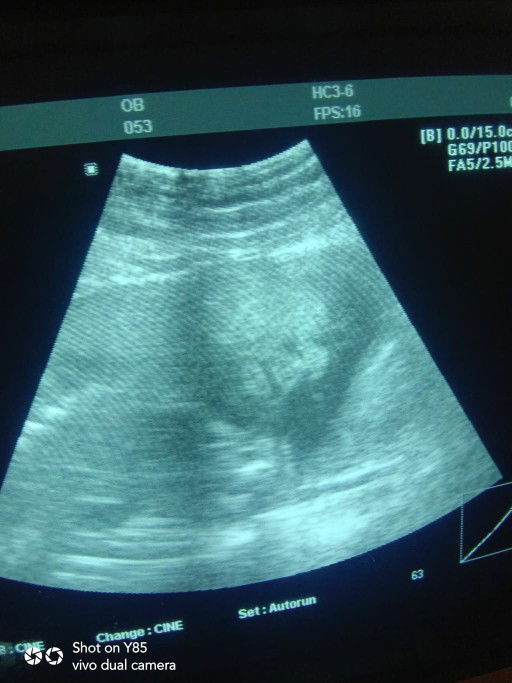

yan daw po yung mukha ni baby sabi ni ob nakita niyo din po ba mukha ng baby niyo nung Ultrasoun ? ?❣️

Sa ob ko, libre 3d/4d ultrasound kada check up kaya nakita ko rin mukha ni baby ❤️

opo.kita po sa ultrasound ang mukha ng baby.